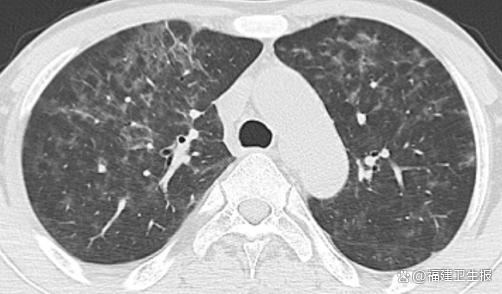

入院后的一系列检查很快揭示了令人震惊的事实:因为长期抗排斥治疗,导致钱先生的免疫力极低。更糟糕的是,淋巴细胞计数低下,炎症指标升高,胸部CT显示出肺部弥漫性斑片状、磨玻璃样的密度增高影,这是肺部感染的典型征象。

接诊的呼吸内科副主任医师林秀华通过支气管镜下肺泡灌洗术,最终锁定了背后的元凶:耶氏肺孢子菌肺炎。